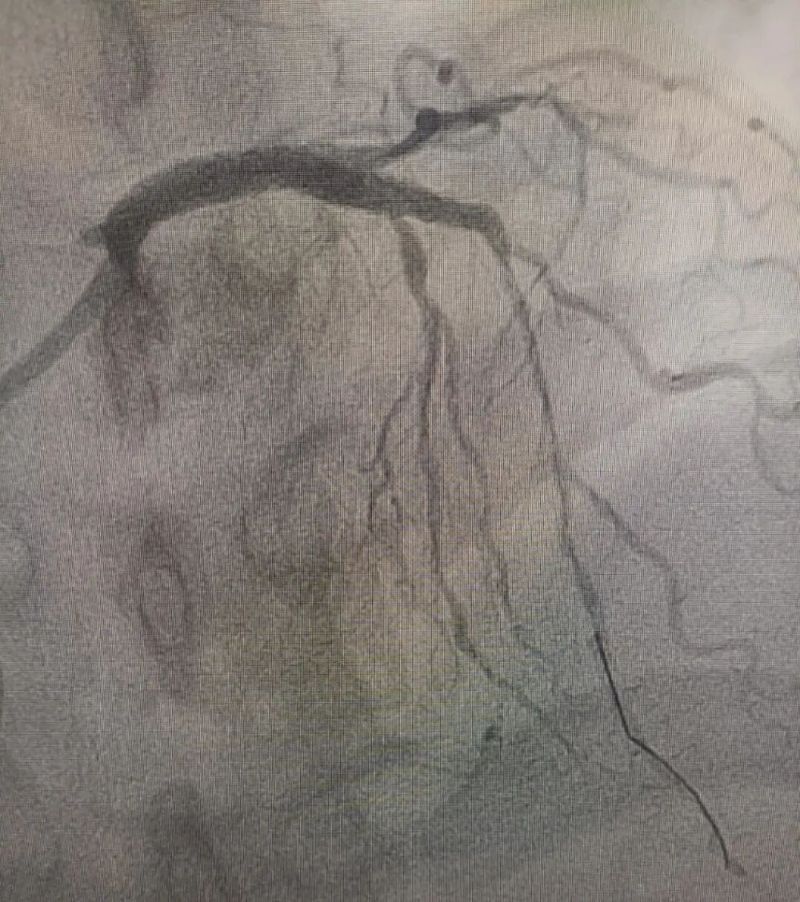

術(shù)中造影顯示,左主干至前降支近段重度狹窄——這正是導(dǎo)致心臟缺血、誘發(fā)室顫的“罪魁禍?zhǔn)住?。主動脈球囊反搏植入、球囊擴張、支架植入......介入團隊精準(zhǔn)操作,一氣呵成。堵塞的血管順利開通,血流重新涌動,這顆一度瀕臨停跳的心臟終于重獲生機。

冠狀動脈造影圖

術(shù)前 (左主干至前降支近段重度狹窄)